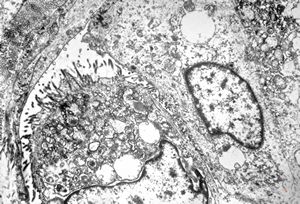

F,38y. | ovary - adenocarcinoma